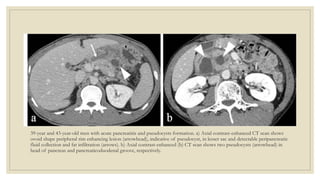

39-year and 43-year-old men with acute pancreatitis and pseudocysts formation. a) Axial contrast-enhanced CT scan shows

ovoid shape peripheral rim enhancing lesion (arrowhead), indicative of pseudocyst, in lesser sac and detectable peripancreatic

fluid collection and fat infiltration (arrows). b) Axial contrast-enhanced (b) CT scan shows two pseudocysts (arrowhead) in

head of pancreas and pancreaticoduodenal groove, respectively.

39-year and 43-year-oldmen with acute pancreatitis and pseudocysts formation. a) Axial contrast-enhanced CT scan shows ovoid shape peripheral rim enhancing lesion (arrowhead), indicative of pseudocyst, in lesser sac and detectable peripancreatic fluid collection and fat infiltration (arrows). b) Axial contrast-enhanced (b) CT scan shows two pseudocysts (arrowhead) in head of pancreas and pancreaticoduodenal groove, respectively.